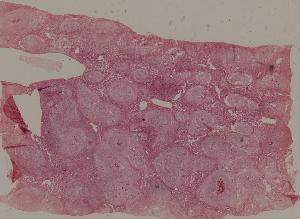

77. Chronic pyelonephritis